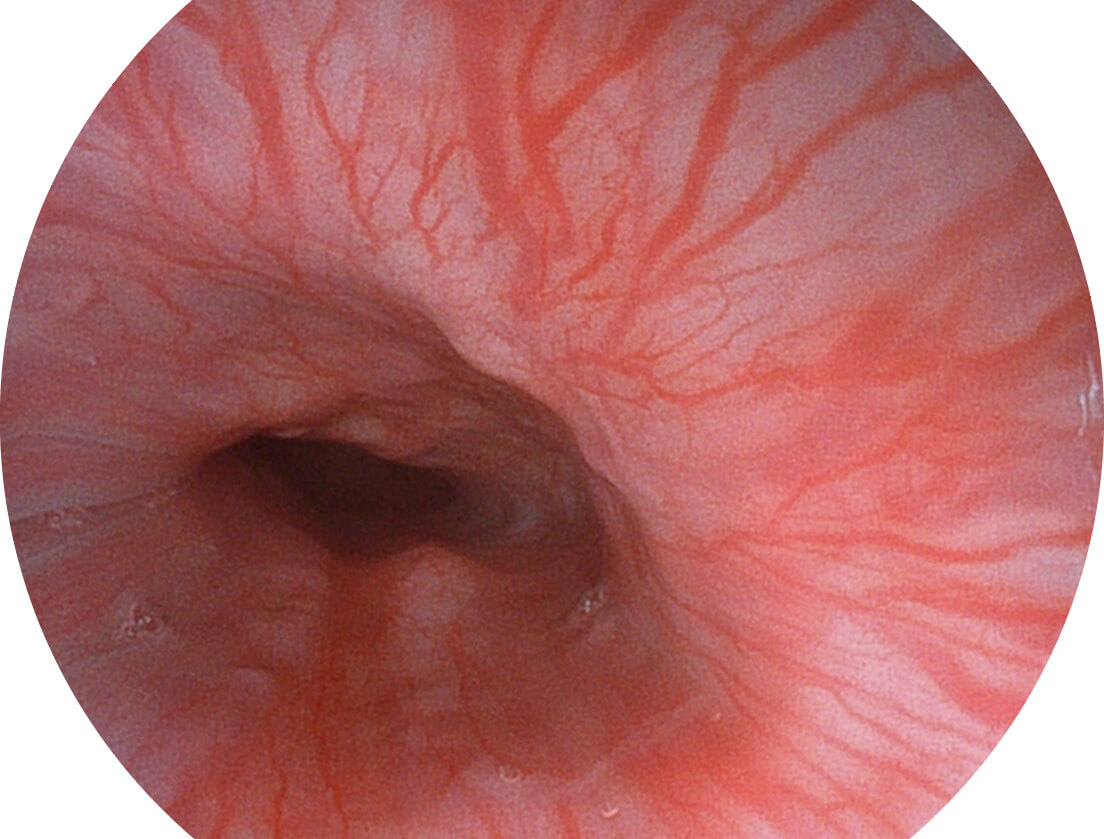

白光图像

VIST图像

采用光路合束技术,光谱自由度高,实现了更丰富的照明模式,染色模式SFI及VIST,从远景到近景,助力消化道早期疾病诊断。